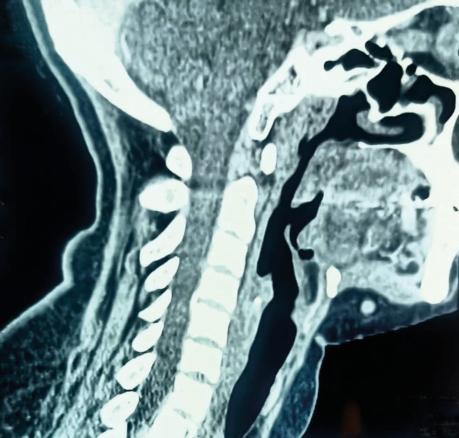

Une patiente âgée de 40 ans est admise à l’hôpital pour exploration d’adénopathies cervicales. L’interrogatoire révèle une obstruction nasale chronique accompagnée d’une rhinorrhée. L’endoscopie met en évidence une rhinite croûteuse avec un bombement du cavum (fig. 1). La tomodensitométrie montre un cavum pseudotumoral (fig. 2, 3 et 4). L’histologie objective un processus granulomateux tuberculoïde (fig. 5). Le GeneXpert sur fragment de biopsie, l’intradermoréaction à la tuberculine et la recherche de bacille de Koch dans les crachats sont négatifs.

La calcémie, la protéine C-réactive (CRP), l’angiotensine convertase et le bilan immunologique sont normaux. La confrontation des données cliniques, radiologiques, histologiques et biologiques retient le diagnostic de sarcoïdose. L’évolution a été favorable sous corticothérapie systémique.